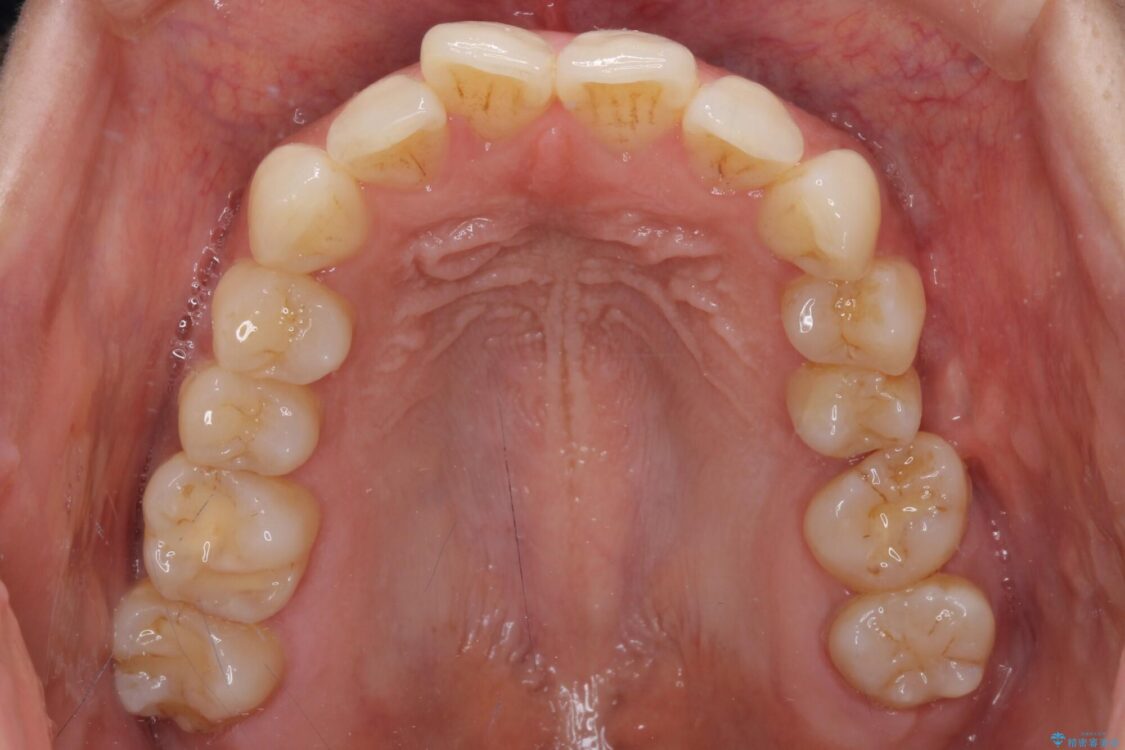

全体的なデコボコと、以前抜歯した歯のスペースを閉じた部分が気になるとのことで来院された患者様です。

左上第一大臼歯を抜歯した際に、スペースを閉じたそうですが、歯が傾斜してものが挟まって不快とのことでした。

インビザライン矯正で全体の歯列と整えるとともに、左上第一大臼歯部にはスペースを作り、インプラントによる補綴治療を行うこととしました。

治療前

• インビザラインによる矯正治療と奥歯のインプラント治療 治療前画像